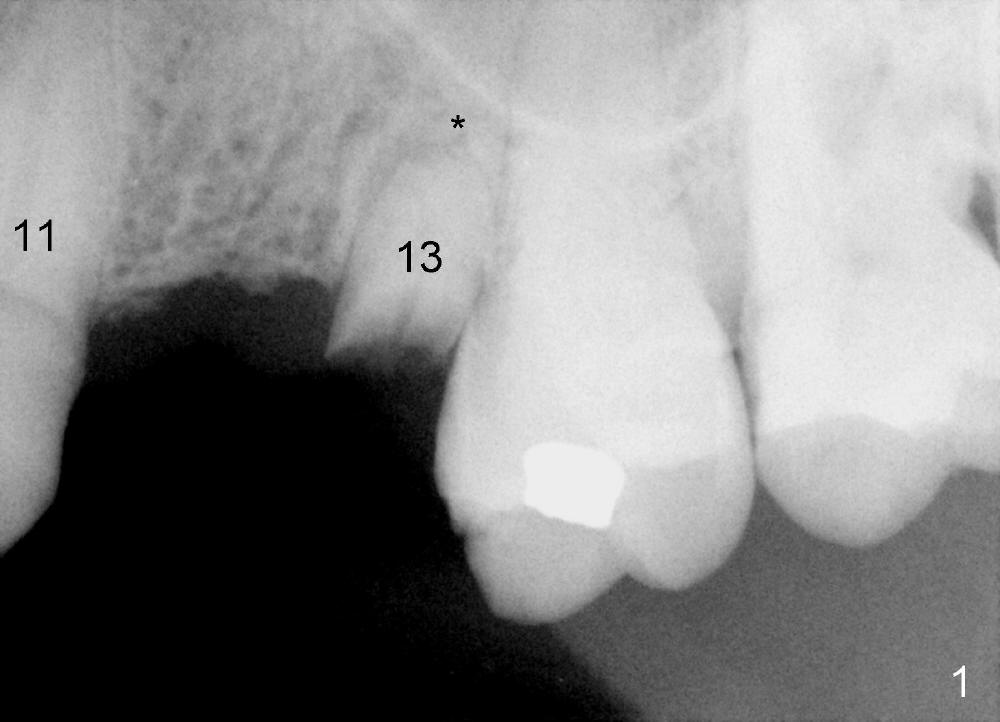

A 77-year-old man dislodged a bridge involving the teeth #11-13 5 years ago (Fig.1).  It was recemented.  Recently it is dislodged again.  The patient agrees to have a definitive treatment to support the lower right quadrant reconstruction.

The anterior retainer is kept as a crown at #11 (Fig.2: C), whereas the residual root at the site of #13 is extracted with apical perforation (Fig.3 ^).  It is confirmed by Fig.4 (<).  To close the perforation, an osteotomy is initiated on the palatal wall of the socket with a 2 mm osteotome (Fig.5 insert: circle).  As the osteotomy is being enlarged by a 3 mm osteotome, the bone between the original socket and the osteotomy is being pushed buccally.  The former is being closed (Fig.5).  The osteotomy is finished with combination of osteotomes and reamers.  Fig.6 shows that a 5x14 mm tap is inserted at the site of #13 and that the sinus floor is lifted.  In fact the sinus membrane is partially torn at the osteotomy, which is repaired by insertion of Colla-form Dressing (Impladent), followed by autogenous bone (harvested from reamers) mixed with Osteogen  (Impladent).  A 5x14 mm implant is placed at the site of #13 with insertion torque more than 60 Ncm (Fig.7: I).  An incision is made at the site of #12 to start osteotomy with insertion of a parallel pin (Fig.7 P).  A 3 mm reamer is kept in place for position confirmation (Fig.8 R).  Due to ridge atrophy (Fig.2 arrowheads), a much smaller, but longer implant is placed at the site of #12 (Fig.9: 4x17 mm).  The autogenous bone harvested from #12 osteotomy is placed in the buccal gap of #13, followed by insertion of Colla-form Dressing (Fig.10 M).  To protect the membrane, a short abutment (4x3 mm) is temporarily placed (Fig.9,10 A) and perio dressing (Fig.9 D) is applied around the abutment and the interproximal areas of the neighboring teeth.  Usually perio dressing dislodges around 1 week postop, particularly for a large edentulous space.  In this case, the dressing is quite stable 11 days postop: the abutment (Fig.11 A) appears to contribute to retention of the dressing (D).